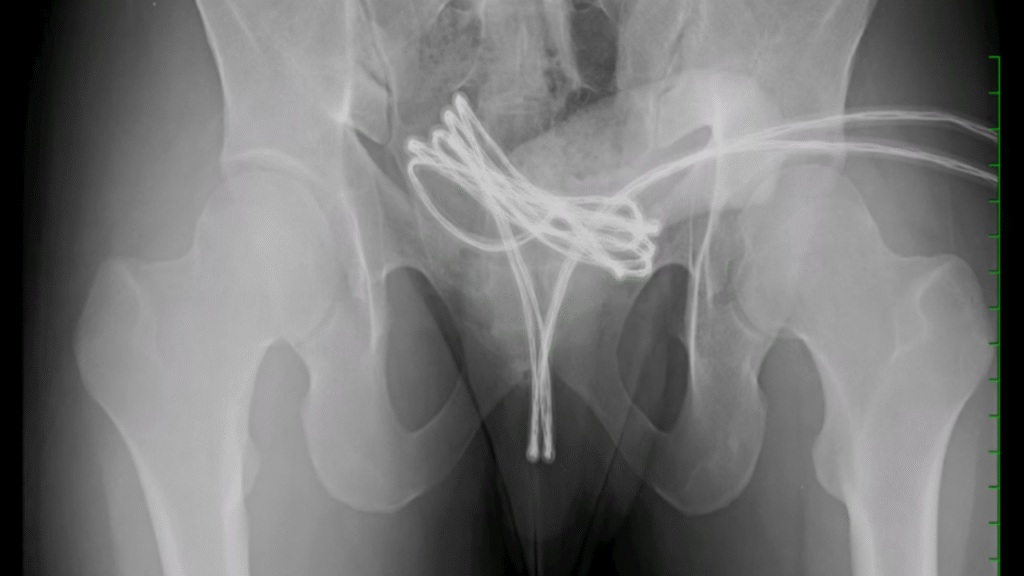

Um jovem de 21 anos precisou passar por cirurgia após introduzir um cabo USB no pênis durante uma prática de estímulo sexual. O caso, ocorrido nos Estados Unidos, envolveu um estudante que procurou atendimento de emergência ao perceber que não conseguiria remover o objeto, inserido em formato de laço com as pontas para fora da uretra.

Segundo os médicos do Drexel University College of Medicine, na Pensilvânia, o cabo avançou até a bexiga, o que tornou a remoção ainda mais delicada. A equipe médica relatou o caso na revista científica Cureus, alertando para os riscos da prática conhecida como sounding  a introdução de objetos longos e finos na uretra para prazer sexual.

O jovem admitiu que já havia inserido outros itens, como cotonetes e cabos de aço, mas sempre conseguiu retirá-los sem ajuda médica. Desta vez, no entanto, a profundidade e a posição do cabo exigiram uma cirurgia para evitar danos maiores.